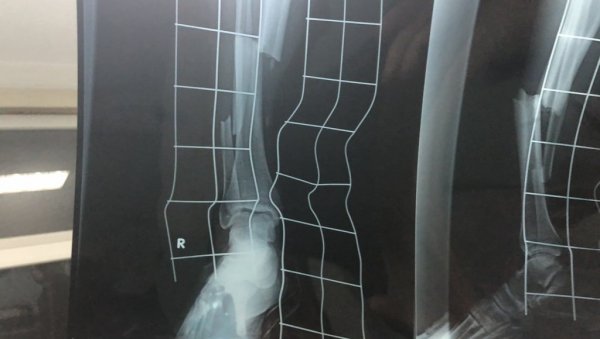

Nije mogao da stane na povređenu nogu, a prelom je bio očigledan.

Nakon hitne intervencije,V.P. je prebačen u bolnicu u Smederevu, gde je potvrđeno da ima prelom obe potkolenične kosti.

Operacija je zakazana za ponedeljak na ortopediji Banjici u Beogradu.